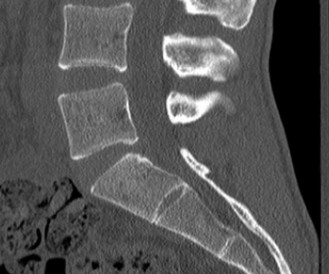

CASE 1 A 63-year-old male sustained a hyperextension injury to his neck while diving into a pool. Upon presentation, he reports decreased sensation in his hands and decreased strength in his arms and wrists, but no lower extremity complaints. On motor examination, he has 5/5 strength in his deltoids and elbow flexors and 4/5 strength in the elbow extensors, wrist extensors, and finger flexors. Lower extremity motor examination is normal. Sensation is decreased to light touch in both hands. Otherwise his sensation is preserved. Images of his cervical spine are shown in Figures 1–1 to 1–3.

Figure 1–2

The correct answer is (B). The clinical scenario describes a patient with central cord syndrome (CCS). CCS continues to be the most common incomplete spinal cord injury accounting for 15.7% to 25% of all spinal cord injuries. The characteristic presentation is an extension moment injury in a previously spondylotic and stenotic spine. Figures 1–1 to 1–3 demonstrate a spondylotic spine with central narrowing and CSF effacement that is worst at the C3–4 level. Bleeding, edema, and/or Wallerian degeneration lead to damage of the lateral corticospinal tract which is the main descending motor tract in the spinal cord. The more central anatomic position of the homunculus to the upper extremities places them at greater risk than those to the lower extremities. As such, injury to the lateral corticospinal tract is characterized by upper more than lower extremity involvement and motor deficits being more pronounced than sensory deficits.